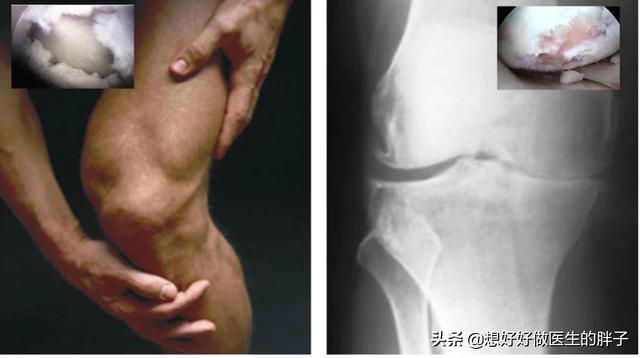

到了关节软骨磨损的晚期,很可能关节内负重区的软骨已经被磨得消失殆尽了。所以患者的关节往往会出现明显的间隙狭窄和大量的骨赘形成,此时的患者,严重的关节屈伸角度也会有明显的受限,而且疼痛会对患者的整个生活造成非常大的困扰,有些比较重的患者甚至会出现休息的时候关节也疼痛,而且在夜间休息的时候能疼醒,此时以前的一些治疗方法就很难帮助患者解决问题了,进行关节置换或者是部分关节置换,是解决患者问题的最佳措施(康复锻炼一样要做)